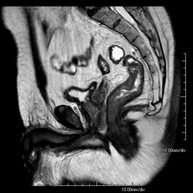

- RM Pelvis femenina

Prueba diagnóstica no invasiva que consiste en la obtención de imágenes de alta definición anatómica de la pelvis mediante el empleo de un campo electromagnético y ondas de radio (con un emisor y un receptor). No utiliza radiación ionizante. Se realiza para estudiar patologías del útero, del ovario, de las trompas y la vagina, ya sean de origen tumoral, inflamatorio o vasculares. Además permite valorar les estructuras adyacentes localizadas en la pelvis, identificando sus alteraciones. A veces requiere el uso de contraste intravenoso (Gadolinio) para caracterizar las lesiones.